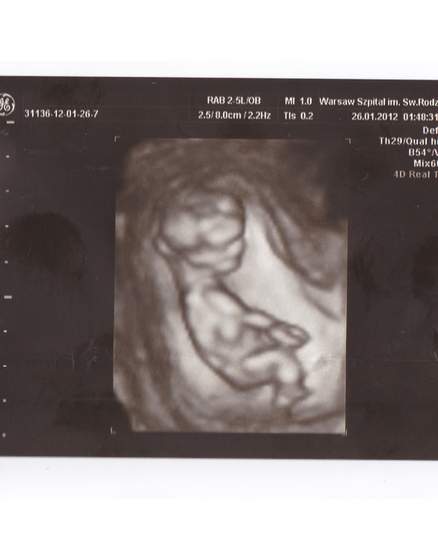

, ale to dopiero 17.02 będzie pierwsze podejście....

Partner będzie mógł być tak czy siak, niezależnie od rodzaju USG.